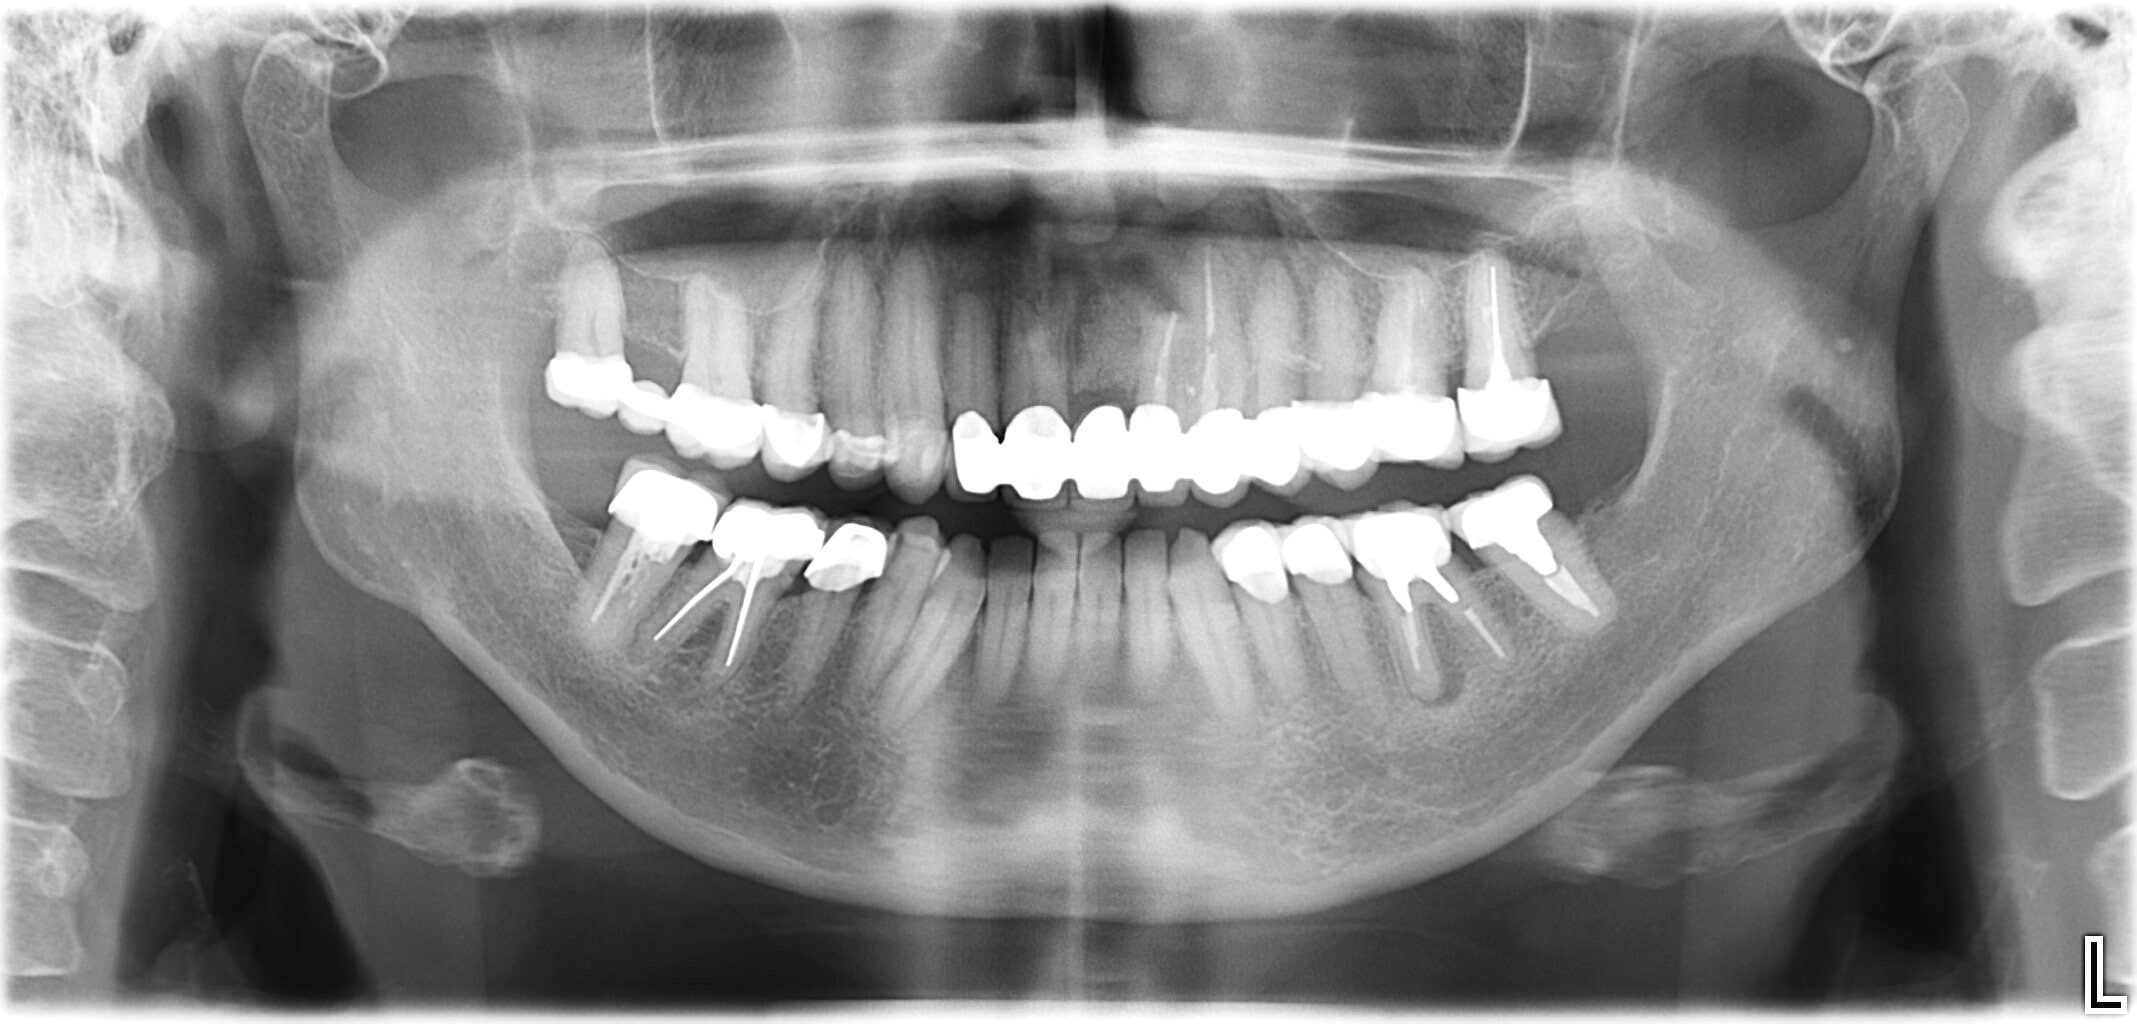

Wenn bei einer unvollständigen Zahnreihe nur ein oder zwei Zähne fehlen, sind meist Implantate die richtige Lösung.

Bei einer Implantation werden künstliche Zahnwurzeln eingepflanzt. Daran können Zahnkronen befestigt werden. Ein Beschleifen der Nachbarzähne (wie es bei herkömmlichen Brücken oft nötig ist) ist dabei nicht notwendig.

Das Problem

- Innerhalb einer Zahnreihe fehlen ein oder mehrere Zähne

- Die Lücke ist beidseitig von natürlichen Zähnen begrenzt

- Nachbarzähne kippen in die Lücke

- Zähne im Gegenkiefer wachsen in Richtung Lücke

- Kaufähigkeit ist beeinträchtigt

Die Lösung

- Implantatgetragener Zahnersatz anstelle einer Brücke oder herausnehmbarer Teilprothese

- Fehlende Zähne werden Zahn-für-Zahn mit Implantaten ersetzt